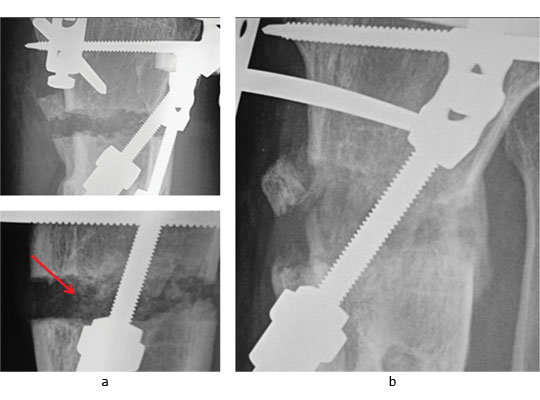

The potential of this approach is seen in the challenging case of a 51-year-old presenting with the combination of established proximal tibial malunion and ACL defi cient instability can be challenging to treat. The patient had a long standing varus malunion and a 3 cm shortening of his tibia presented with pain, instability and deformity. The patient’s medial compartment was bereft of any articular cartilage. We used a modified Taylor Spatial Frame for osteogenesis which we augmented with stem cell therapy. Application of a Taylor Spatial Frame in combination with tibial and fibular osteotomies was followed with distraction osteogenesis at a rate of 1 mm per day, commenced the day after the tibial and fibular corticotomies. We supplemented the standard treatment with stem cell therapy one week following corticotomies. Autologous PBSC were harvested from the patient and injected percutaneously into the corticotomy sites. We were able to demonstrate callus formation two weeks after distraction osteogenesis (one week after injection of PBSC, Fig.4a). Two further weekly injections of PBSC were given during the osteogenesis process and almost complete healing was seen at four months (Fig.4b). Although a similar result could have been easily achieved without the injection of PBSC there is the potential to reduce frame time and morbidity associated with extended frame wear. At final follow-up the patient did not have any equinus deformity of the ankle or a loss of initial knee movement, regaining 50° of knee range of movement following the distraction osteogenesis. A second-stage arthroscopy with subchondral drilling and allograft ACL reconstruction was performed for chondrogenesis and stabilisation of his knee. We did not see any premature closing of the corticotomy with the use of PBSC and we believe that PBSC may have a significant future role in malunion and nonunion surgery.

Fig. 4 Radiographs of a 51-yearold man who presented with left knee pain and instability, showing a) distraction osteogenesis and evidence of callus formation one week after injection of PBSC into corticotomy site (red arrow), and b) signifi cant growth of new bone after four months.